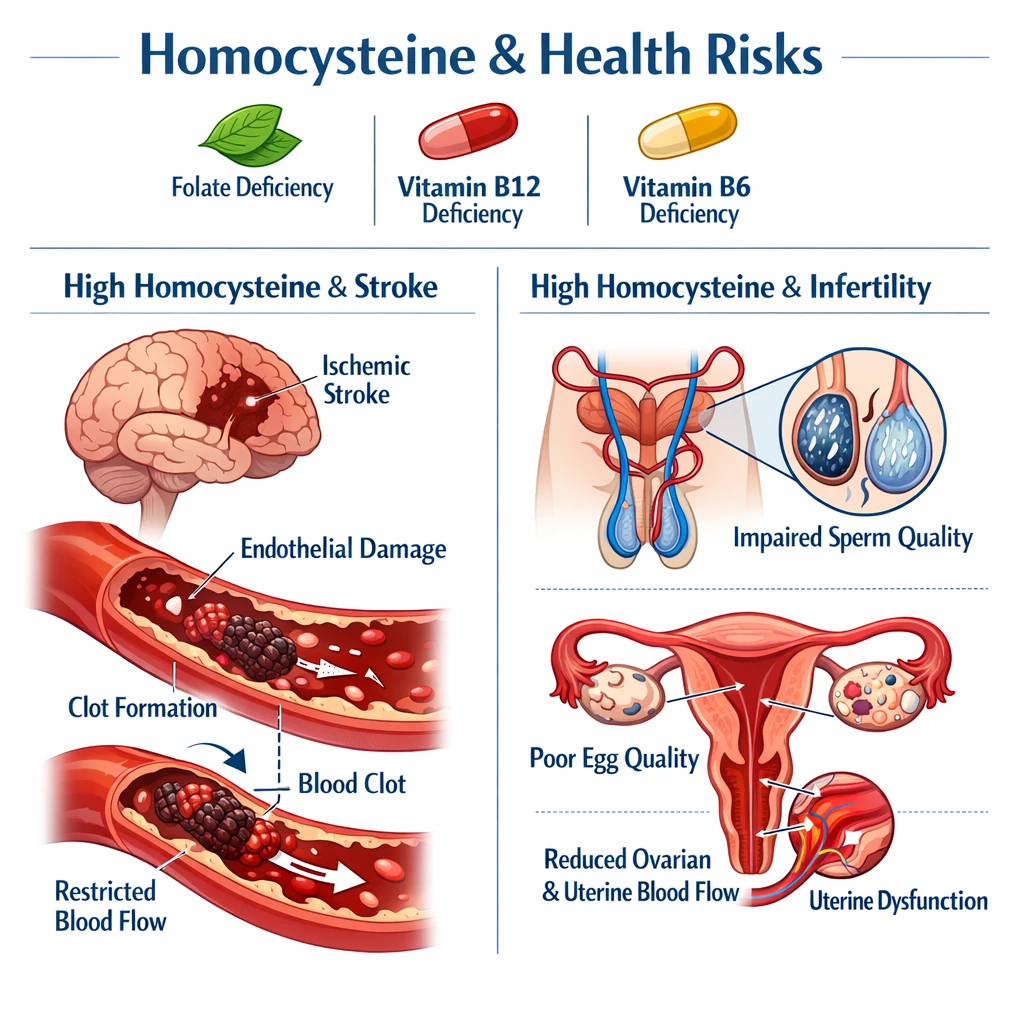

ANA مثبت؛ نشانه فعال شدن خودایمنی

آزمایش ANA (Antinuclear Antibody) شاخص عمومی فعالیت خودایمنی است و وقتی در بیمار مبتلا به پارکینسونیسم دارویی دیده میشود، پزشک را به سمت احتمال لوپوس دارویی هدایت میکند.

ویژگیهای مهم ANA در این زمینه:

– معمولاً تیتر پایین تا متوسط (مثلاً 1:160)

– الگوی هوموژن یا اسپکلدار (با روش IFA)

– همراهی با آنتیبادی ضد هیستون (Anti‑Histone) در بیش از ۹۰٪ موارد لوپوس دارویی

بنابراین، ANA مثبت تنها یک یافته تصادفی نیست؛ بلکه میتواند بازتاب فعال شدن سیستم ایمنی در پاسخ به تجمع دارویی یا متابولیتهای آن باشد.

در برخی موارد، دو حالت ظاهراً متفاوت — اختلال حرکتی ناشی از دارو و پاسخ خودایمنی — همزمان رخ میدهند. پژوهشهای بالینی نشان دادهاند که ANA مثبت در پارکینسونیسم دارویی میتواند نتیجه فعال شدن مسیرهای ایمنی مرتبط با دارو باشد، بهویژه زمانی که داروی مصرفی (مانند والپروات یا لیتیوم) خود شناختهشده به عنوان محرک لوپوس دارویی است.

مکانیسم احتمالی:

– تغییر ساختار آنتیژنهای سلولی در اثر متابولیت دارو

– تشکیل کمپلکسهای ایمنی در بافتهای عصبی و اندوتلیال

– تحریک سلولهای T و B و تولید آنتیبادیهای ضد هیستون و ANA

– ANA، Anti‑Histone و Anti‑dsDNA

اگر ANA مثبت و Anti‑Histone نیز مثبت باشد، قطع داروی مشکوک معمولاً موجب کاهش تدریجی تیتر آنتیبادی و بهبود تدریجی علائم میشود.

۲. ANA مثبت همیشه به معنی لوپوس است؟

خیر، ANA میتواند در سنین بالا یا برخی بیماریهای دیگر هم مثبت شود؛ تشخیص نهایی نیاز به بررسی ضمیمه Anti‑Histone و الگوی بالینی دارد.